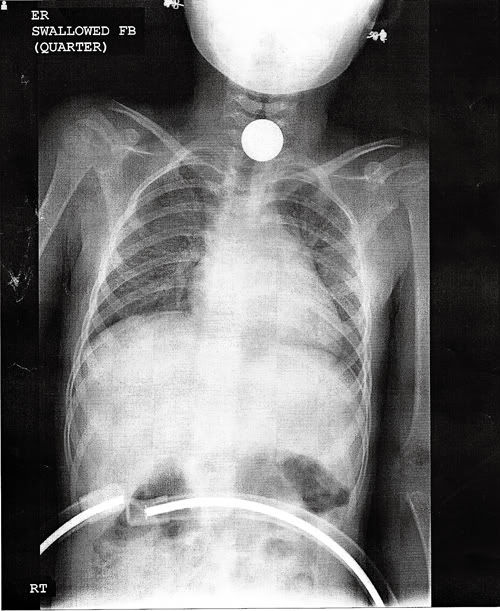

子供と梅垣は鼻に豆突っ込むよな